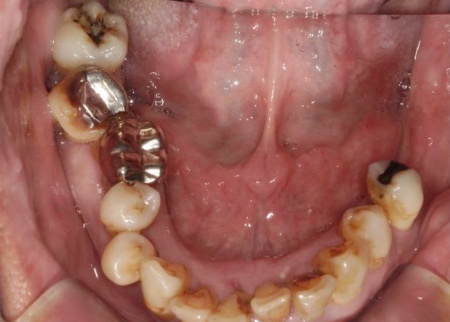

下あごは抜歯後も11本の歯が残りますが、上あごは抜歯後に歯が1本も残らないため、しっかり噛めるようにするには上の歯を補う治療が必要とお伝えし、以下2つの方法を提案しました。

最後に、残っている下の歯としっかりと噛み合っていることを確認し、治療を終了しました。